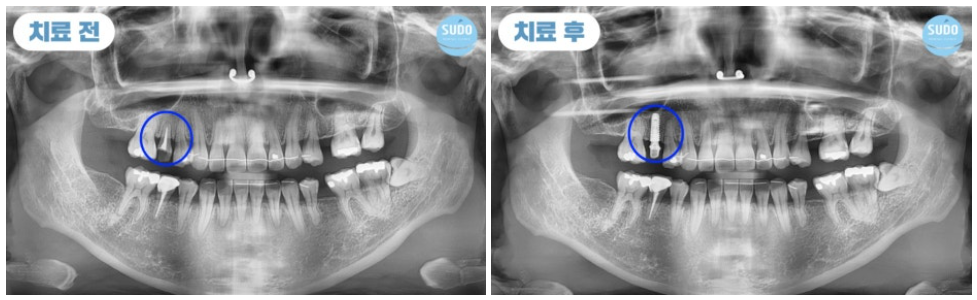

위 환자분은 30대 초반 여성분으로, 고등학생일 때 치료 받았던 금니가 빠져 저희 수도치과에 내원해 주셨습니다.

그 부분만을 확대하여 x-ray 사진 촬영해 본 결과 치아 뿌리 안쪽까지 심한 충치로 인해 발치 후 임플란트를 진행하셔야 하는 상태였습니다. 임플란트 경험이 없으셨던 환자분을 위해 수도치과 의료진들의 충분한 치료 설명을 통해 발치 후 부산영도임플란트 식립 계획을 수립하였습니다.

처음 내원하셨을 때는 외국 거주 중이셨고, 열흘 후에 출국 예정이셨습니다. 이에 따라 내원 당일에 발치 후 즉시 임플란트를 식립하셨고, 주변 치아의 이동을 예방하기 위해 유지 철사를 부착한 후 다시 출국하셨습니다.

임플란트를 식립한 후 11월에 다시 한국을 방문하셨는데, 시간이 제한적이어서 며칠밖에 계시지 못하는 상황이라 부산영도임플란트의 상태를 확인한 후 맞춤형 지대주와 임시치아를 제작하여 장착한 후 다시 출국하셨습니다.

외국에 거주 중이신 분이라 전체적인 치료 기간은 길어졌지만 큰 어려움 없이 마무리되었고, 5개월 정도 임시치아 상태로 편하게 사용하신 후 최근 다시 한국으로 돌아오셔서 최종 보철물까지 마무리할 수 있었습니다.